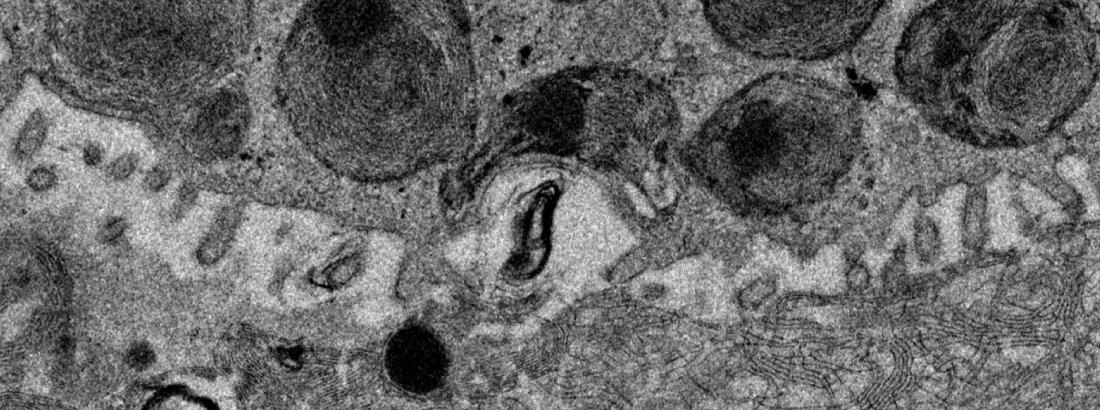

Primary adult human organoids: Long-term culture of alveolar and airway organoids derived from human tissue in defined media conditions

Imaging: Confocal fluorescence microscopy on whole mount stained organoid